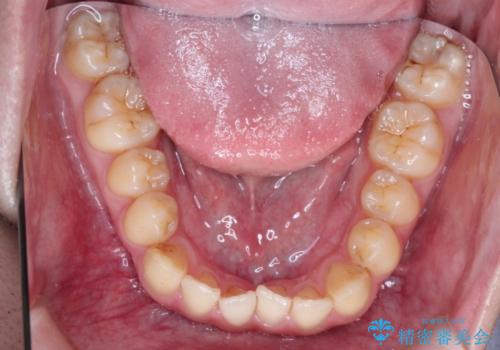

前歯のデコボコ インビザラインによる目立たない矯正

- 前歯のデコボコを主訴に来院された患者様です。

目立たないそうちをご希望されたので、インビザラインにて治療することとしました。

歯と歯の間をわずかに削ってスペースをつくり、デコボコを改善しました。